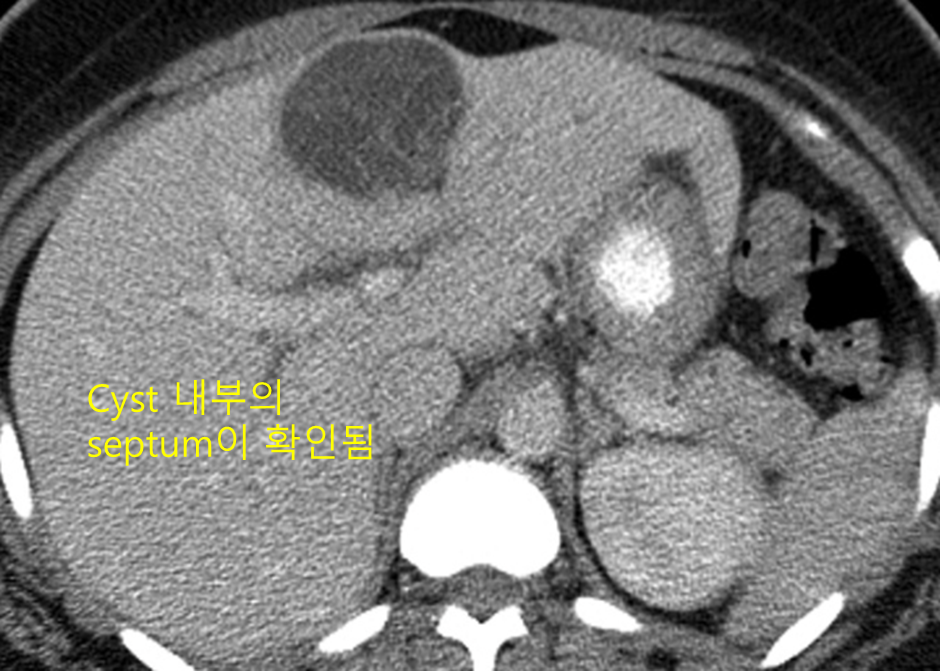

5. 낭샘종(cystadenoma)

1) 개요

(1) Mucinous fluid가 차있는 낭종성 종괴

(2) 10~20cm까지 커질 수 있음

3) 검사소견

(1) US: Cystic mass, with varying wall thickness and multiple septations

(2) CT: Cyst wall과 septum의 조영증강이 두드러짐

4) 치료: 국소적 절제 (cystadenocarcinoma로의 이행 위험성 있음)